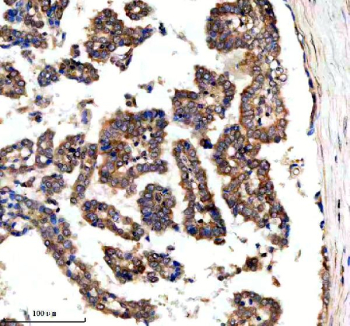

Immunohistochemical staining of SRBD1 using anti-SRBD1 antibody. SRBD1 was detected in a paraffin-embedded section of human lung adenocarcinoma tissue. Heat mediated antigen retrieval was performed in EDTA buffer (pH 8.0, epitope retrieval solution). The tissue section was blocked with 10% goat serum. The tissue section was then incubated with 2 ug/ml rabbit anti-SRBD1 antibody overnight at 4oC. Peroxidase Conjugated Goat Anti-rabbit IgG was used as secondary antibody and incubated for 30 minutes at 37oC. The tissue section was developed using an HRP secondary and DAB substrate.